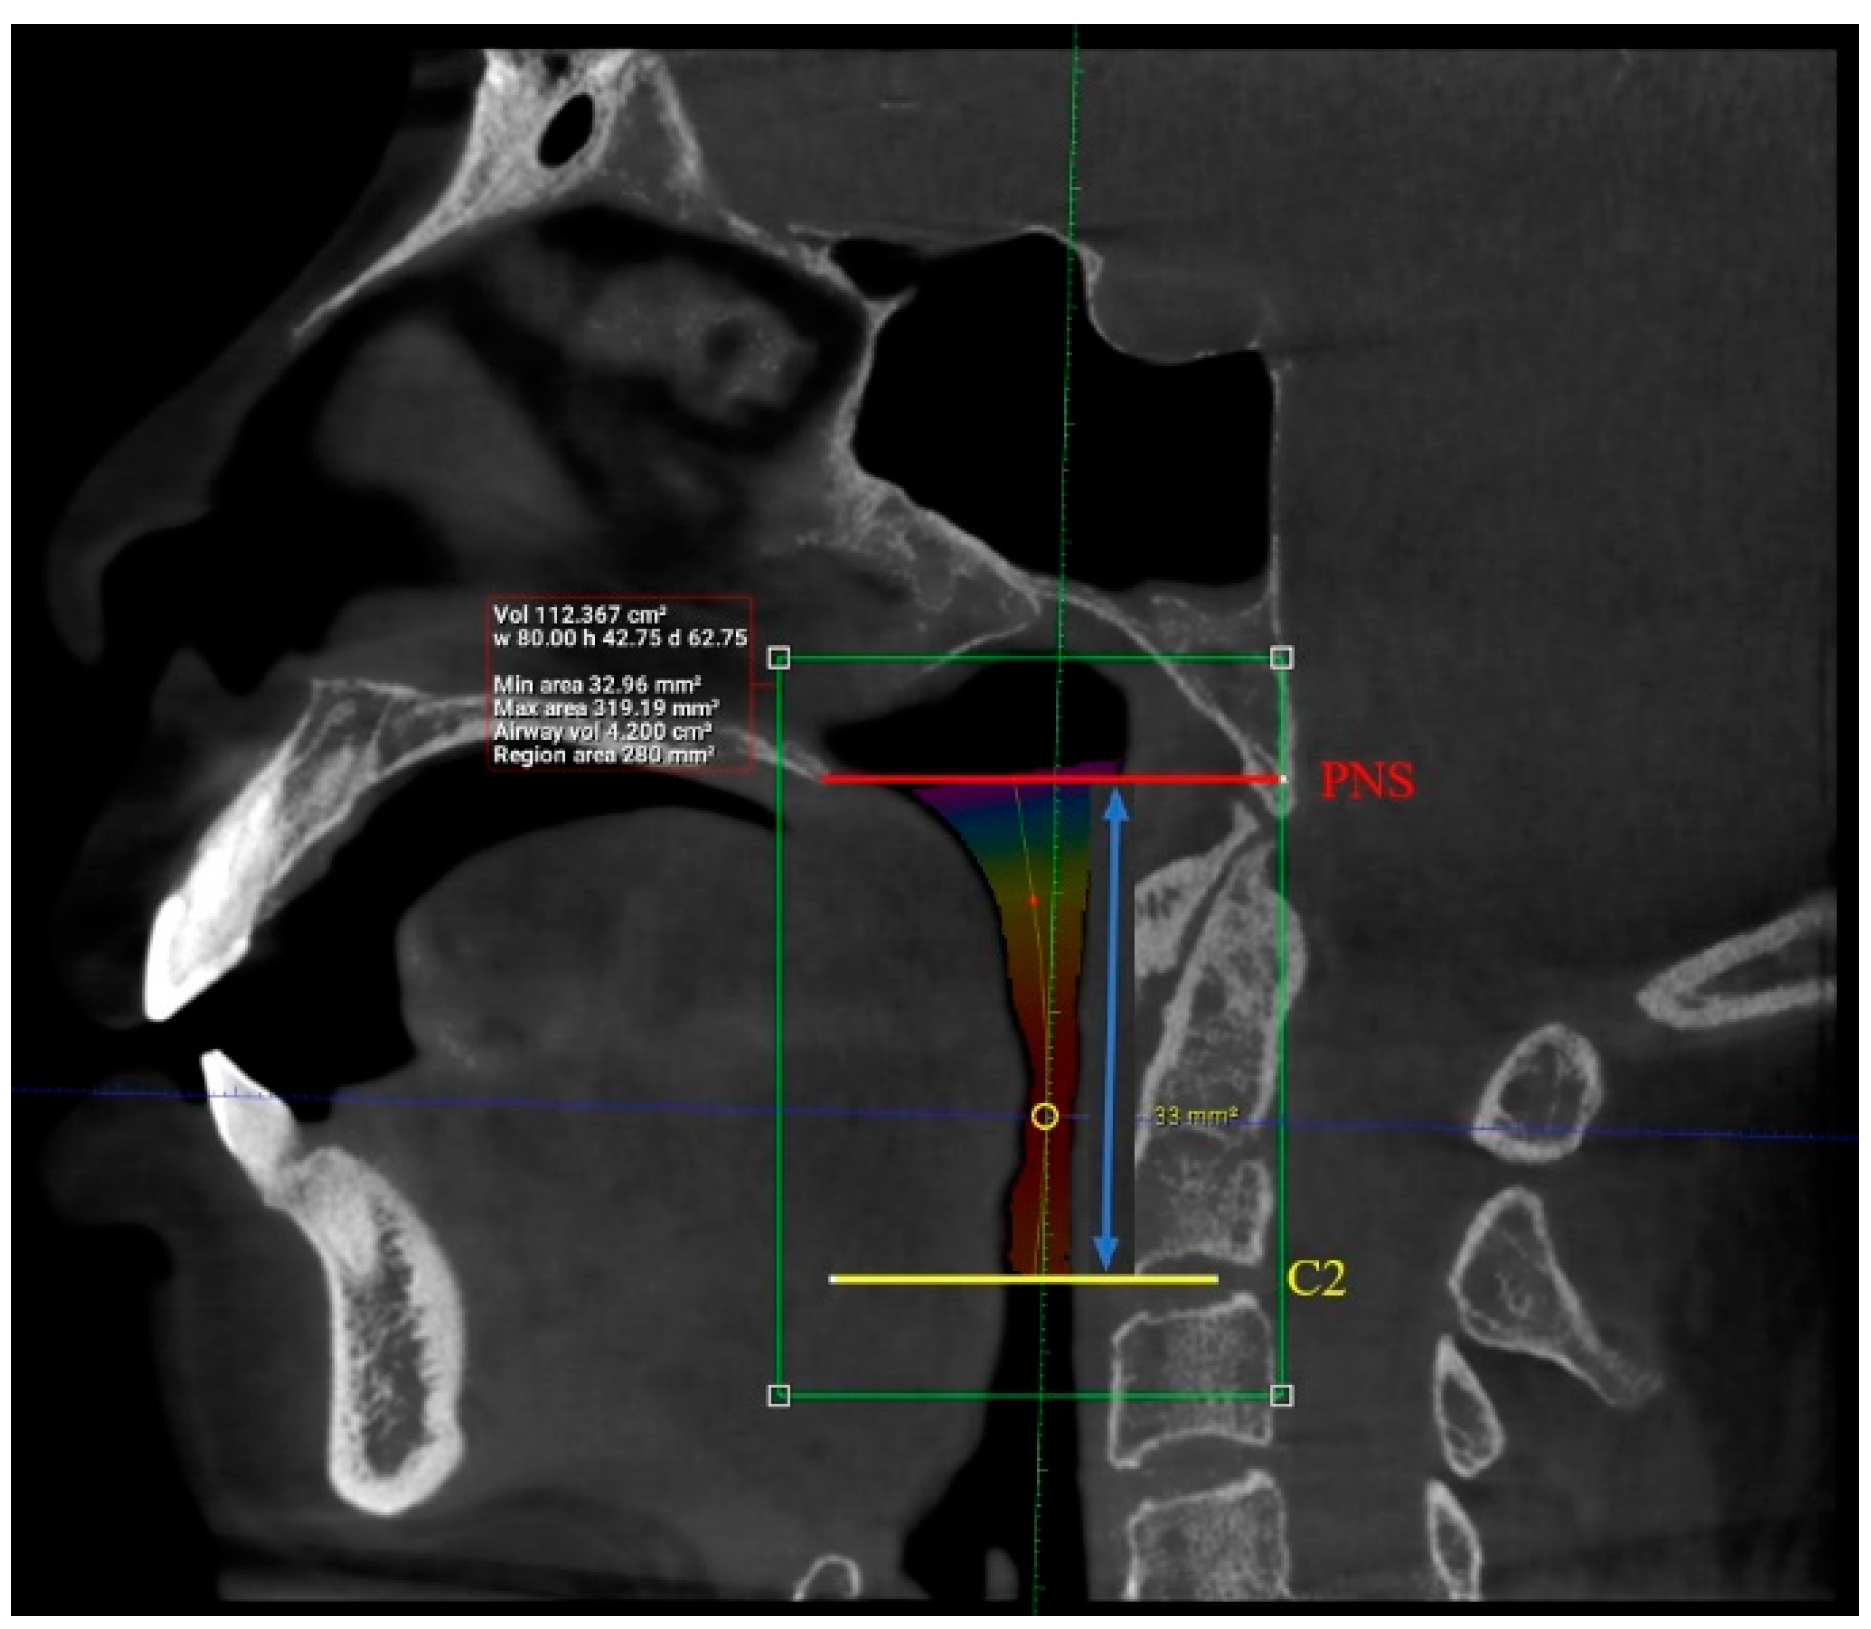

| N | Minimum | Maximum | Mean | Std. Deviation | |

| Length (mm) | 101 | 29.93 | 55.75 | 42.63 | 6.24 |

| Total volume (cm3) | 101 | 94.58 | 173.45 | 131.67 | 17.91 |

| Average volume (cm3) | 101 | 3.34 | 32.09 | 11.10 | 5.21 |

| Antero-posterior (mm) | 101 | 1.00 | 14.50 | 6.44 | 3.19 |

| Width (mm) | 101 | 8.00 | 37.00 | 21.69 | 6.54 |

| Valid N (listwise) | 101 |